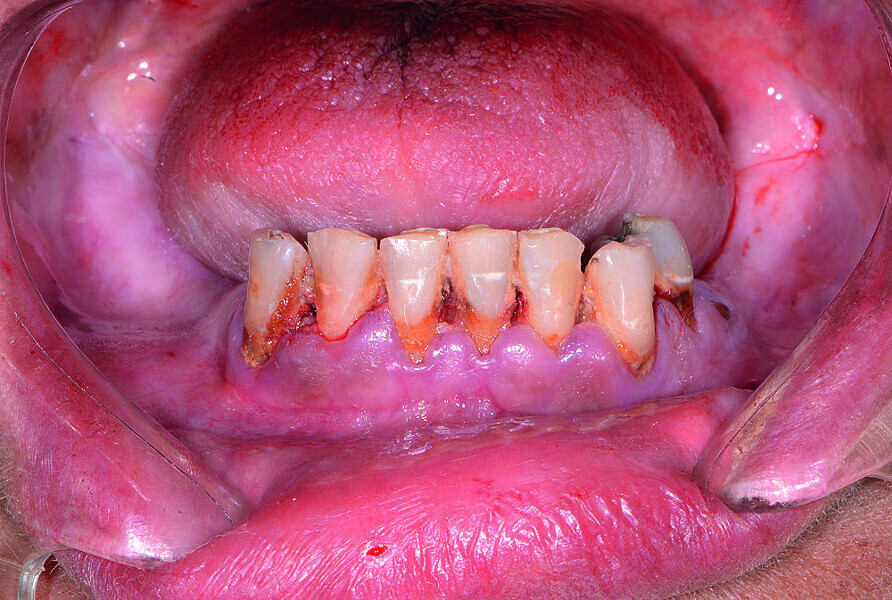

Fig 1 Vue préopératoire avec écarteur de lèvres